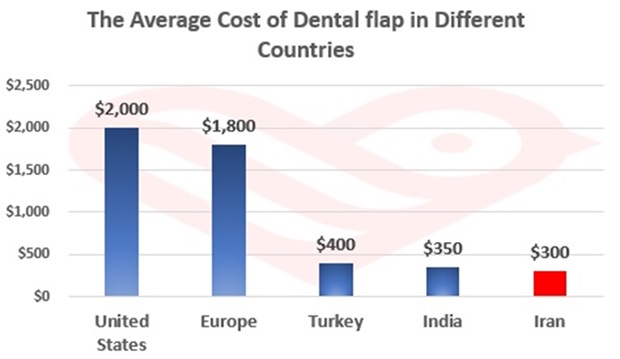

- Cost: Medical and dental procedures in Iran can be more cost-effective compared to many Western countries. This cost advantage may make it an attractive option for individuals seeking periodontal treatment.